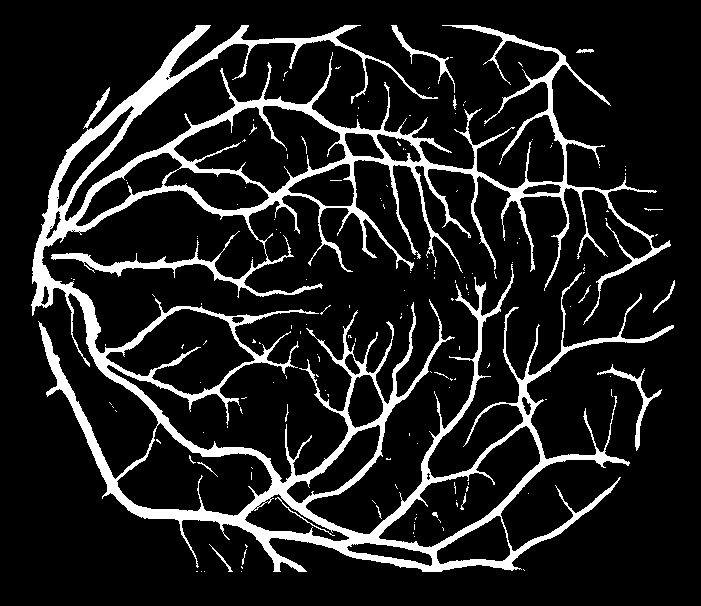

Refer to caption

(a) Original image

(b) Ground truth

(c) Level-I balancing

(d) Level-II balancing

(e) Original image

(f) Ground truth

(g) Level-I balancing

(h) Level-II balancing

Figure 6: Visual results after level-II balancing.

Impact of Level-II Balancing: This section analyzes the impact of applying Level-II balancing on top of Level-I balancing to the same sample images as in the previous sub-section. Specifically, the outcomes of applying Level-I and Level-II balancing are compared and graphically demonstrated in Figure 6. The application of Level-II balancing results in a significant performance boost over Level-I balancing, as indicated by higher values of all performance measures. Similarly, Figure 6 shows the visual outcomes of Level-II balancing for the sample DRIVE images along with their ground truths. The output segmentation masks show the detection of thin retinal blood vessels much closer to the ground truth binary mask than the images for Level-I balancing. The red rectangle is highlighted as a focus area for conveniently comparing the results. It can be concluded from comparing the results that Level-II balancing detects most of the vessel’s pixels, especially thin vessels, thereby significantly improving the sensitivity.